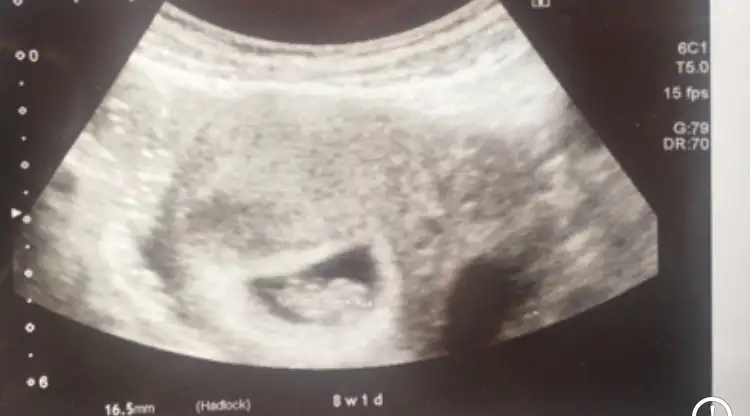

6-7 . haftalara ait ultrason görüntünüz eliniz de varsa inceleyin. Bebek sağ tarafta ya da sağ tarafa daha yakınsa kız , Eğer bebek sol tarafta ya da sol tarafa yakınsa cinsiyeti erkektir.